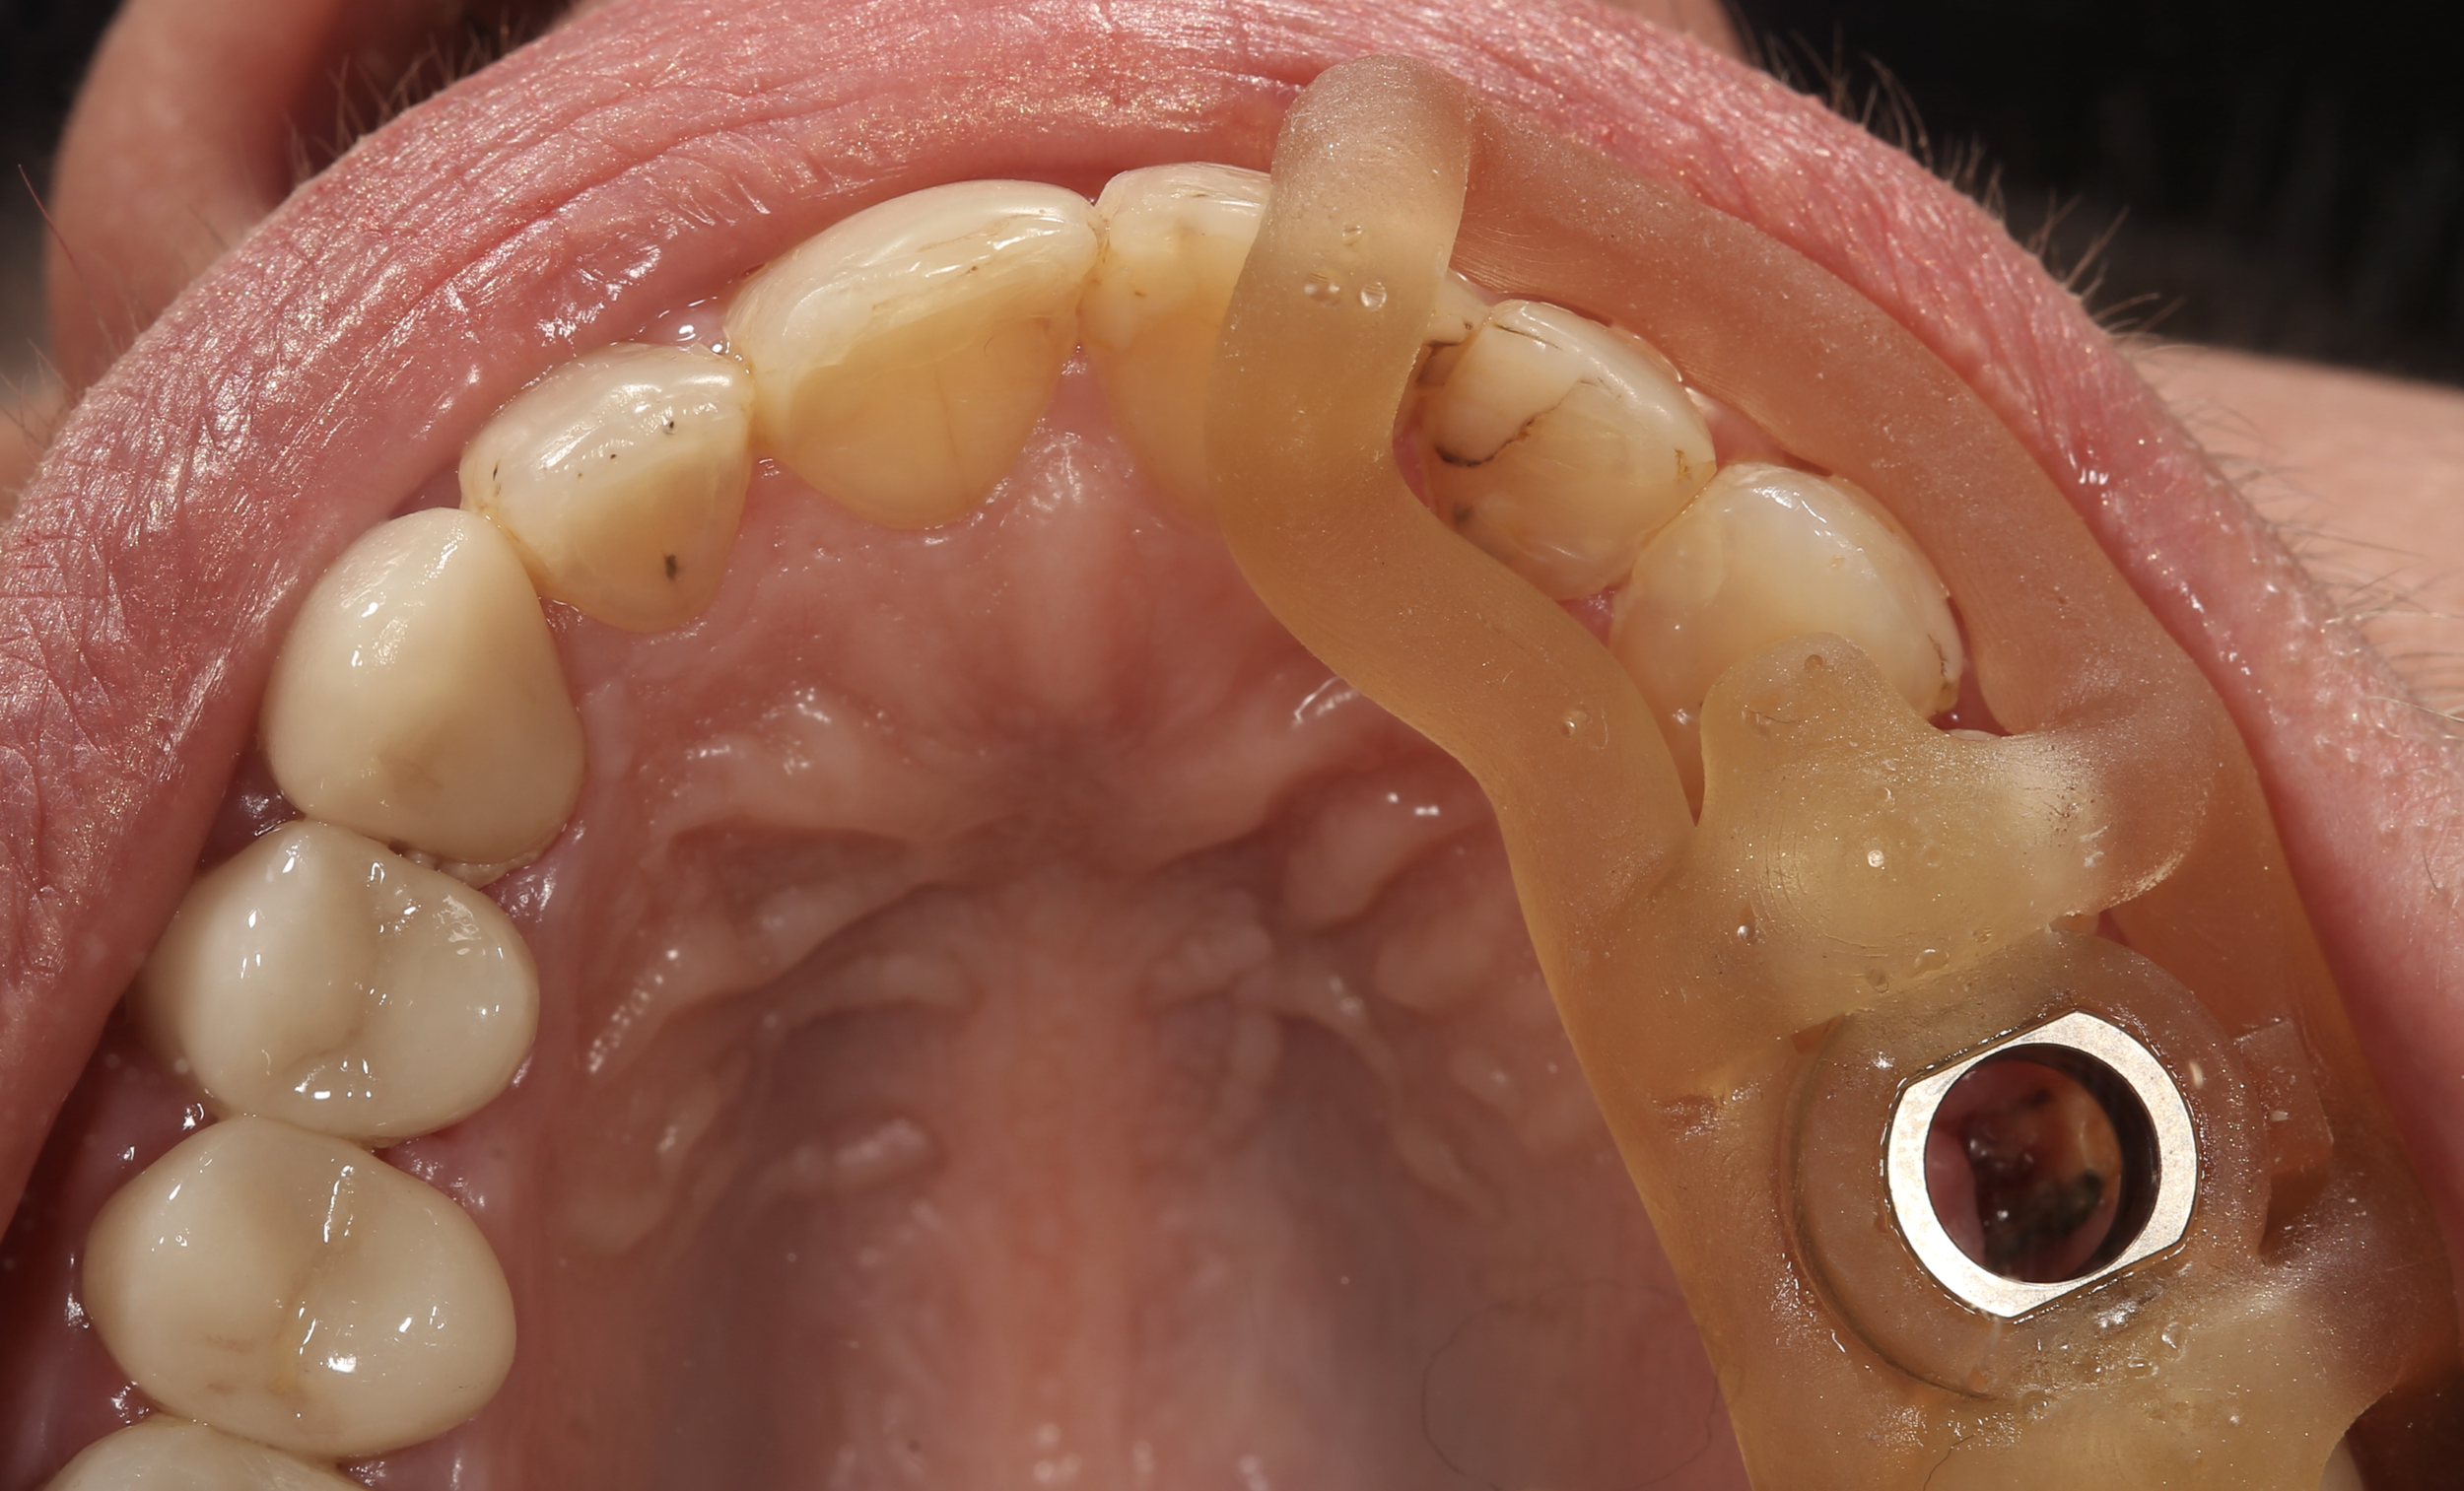

L’apport du numérique aux restaurations implanto portées : pour une pratique quotidienne simplifiée

Si la chirurgie guidée facilite et sécurise le geste implantaire, elle est surtout l’occasion, pour le praticien qui réalisera la prothèse, de valider les axes et les émergences des implants.

La planification, préalable indispensable à la chirurgie guidée est donc un outil essentiel de la communication entre les équipes chirurgicales et prothétiques.